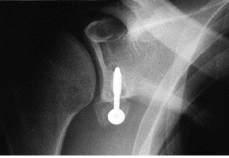

Ninguno de los pacientes intervenidos presentó nuevas luxaciones después de la cirugía. El déficit medio de rotación externa comparando las dos extremidades fue de 9° (* = 6°) y no hubo diferencias significativas en cuanto a rotación interna y la antepulsión. Un 60% de las pastillas estaban en el tercio inferior, el 20% en el tercio medio y otro 20% en el superior (Fig. 1). El 39% estaban enrasadas con el margen anterior de la glena, el 22% se habían colocado externas (Fig. 2) y el 39% se encontraban en situación demasiado medial (Fig. 3). En tan solo uno de los casos se utilizaron dos tornillos para fijar la pastilla ósea. En el resto se utilizó un tornillo pero sólo en la mitad de los casos éste atravesaba las dos corticales (Fig. 4). El tipo de tornillo más utilizado fue el maleolar (n = 18), y en tres casos se implantó un tornillo de escafoides. La mitad de las pastillas mostraban signos de consolidación, mientras que en el resto, el 21% habían migrado (Fig. 5) y el 28% se mantenían en posición merced a una unión fibrosa (Fig. 6). En ningún caso se evidenció osteolisis de la pastilla. Tan solo dos pacientes cumplían todos los parámetros radiográficos ideales. Ningún paciente requirió ser reintervenido por complicaciones clínicas posteriores, o por migración o rotura del tornillo. No se detectaron lesiones vasculonerviosas ni infección postoperatoria en ningún paciente.

Figura 4. Proyección de outlet. Tornillo de escafoides atravesando las dos corticales.